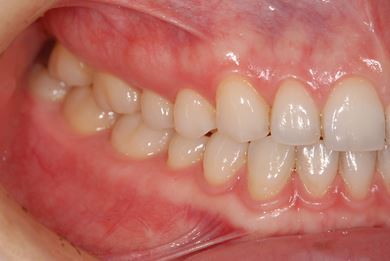

| 性別/年齢 | 女性 / 29歳 | ||||||||||||||||||||||||||||||||

| 主訴 | インプラント治療と、親知らずの抜歯の相談。なるべく安価で、短期間で終了して欲しい。 | ||||||||||||||||||||||||||||||||

| 治療方針 | 欠損部分をインプラント治療にて、機能的・審美的回復を行う。 | ||||||||||||||||||||||||||||||||

| 治療内容 | インプラント1本、メタルボンドセラミッククラウン1本 | ||||||||||||||||||||||||||||||||

| 総治療費 | 252,000円 | ||||||||||||||||||||||||||||||||

| 治療期間 | 11ヶ月 |